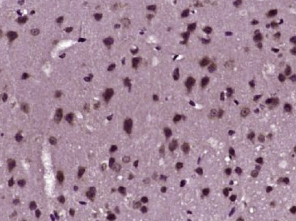

多聚甲醛固定,石蜡包埋(小鼠脑组织);用柠檬酸钠缓冲液(pH6.0)煮沸15min后提取抗原;用3%过氧化氢阻断内源性过氧化物酶20分钟;阻断缓冲液(正常山羊血清)37℃30min;用(BASP1)PYC抗体孵育未结合的克隆抗体在1:400下在4°C下过夜,然后根据SP试剂盒(兔子)说明和DAB染色进行操作。